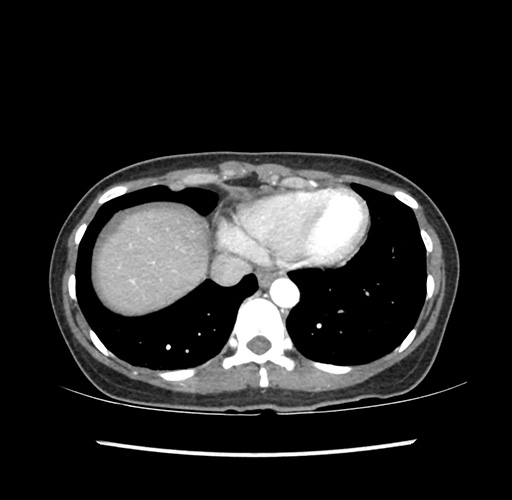

Imaging Analysis

Look through the patient's CT scan to identify any areas of concern for the necessary procedure.

Based on your CT findings, which issue(s) would give reason for "planned slowing down moment(s)" in this case?

Considering a standard left lateral sectionectomy procedure, what step(s) of the operation would you do differently in this case ?